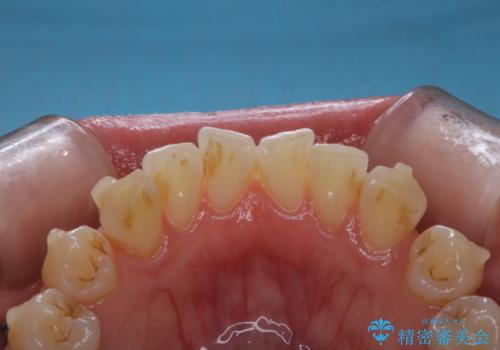

インビザラインでの治療中の患者様のクリーニング前後写真です。

矯正治療中は虫歯や歯周病リスクが高くなります。

矯正治療(インビザライン、ワイヤー矯正)の経過で来院の際、ご希望の場合はクリーニングの予約も同時に取ることが可能です。

ぜひ定期的なクリーニングをおすすめします。